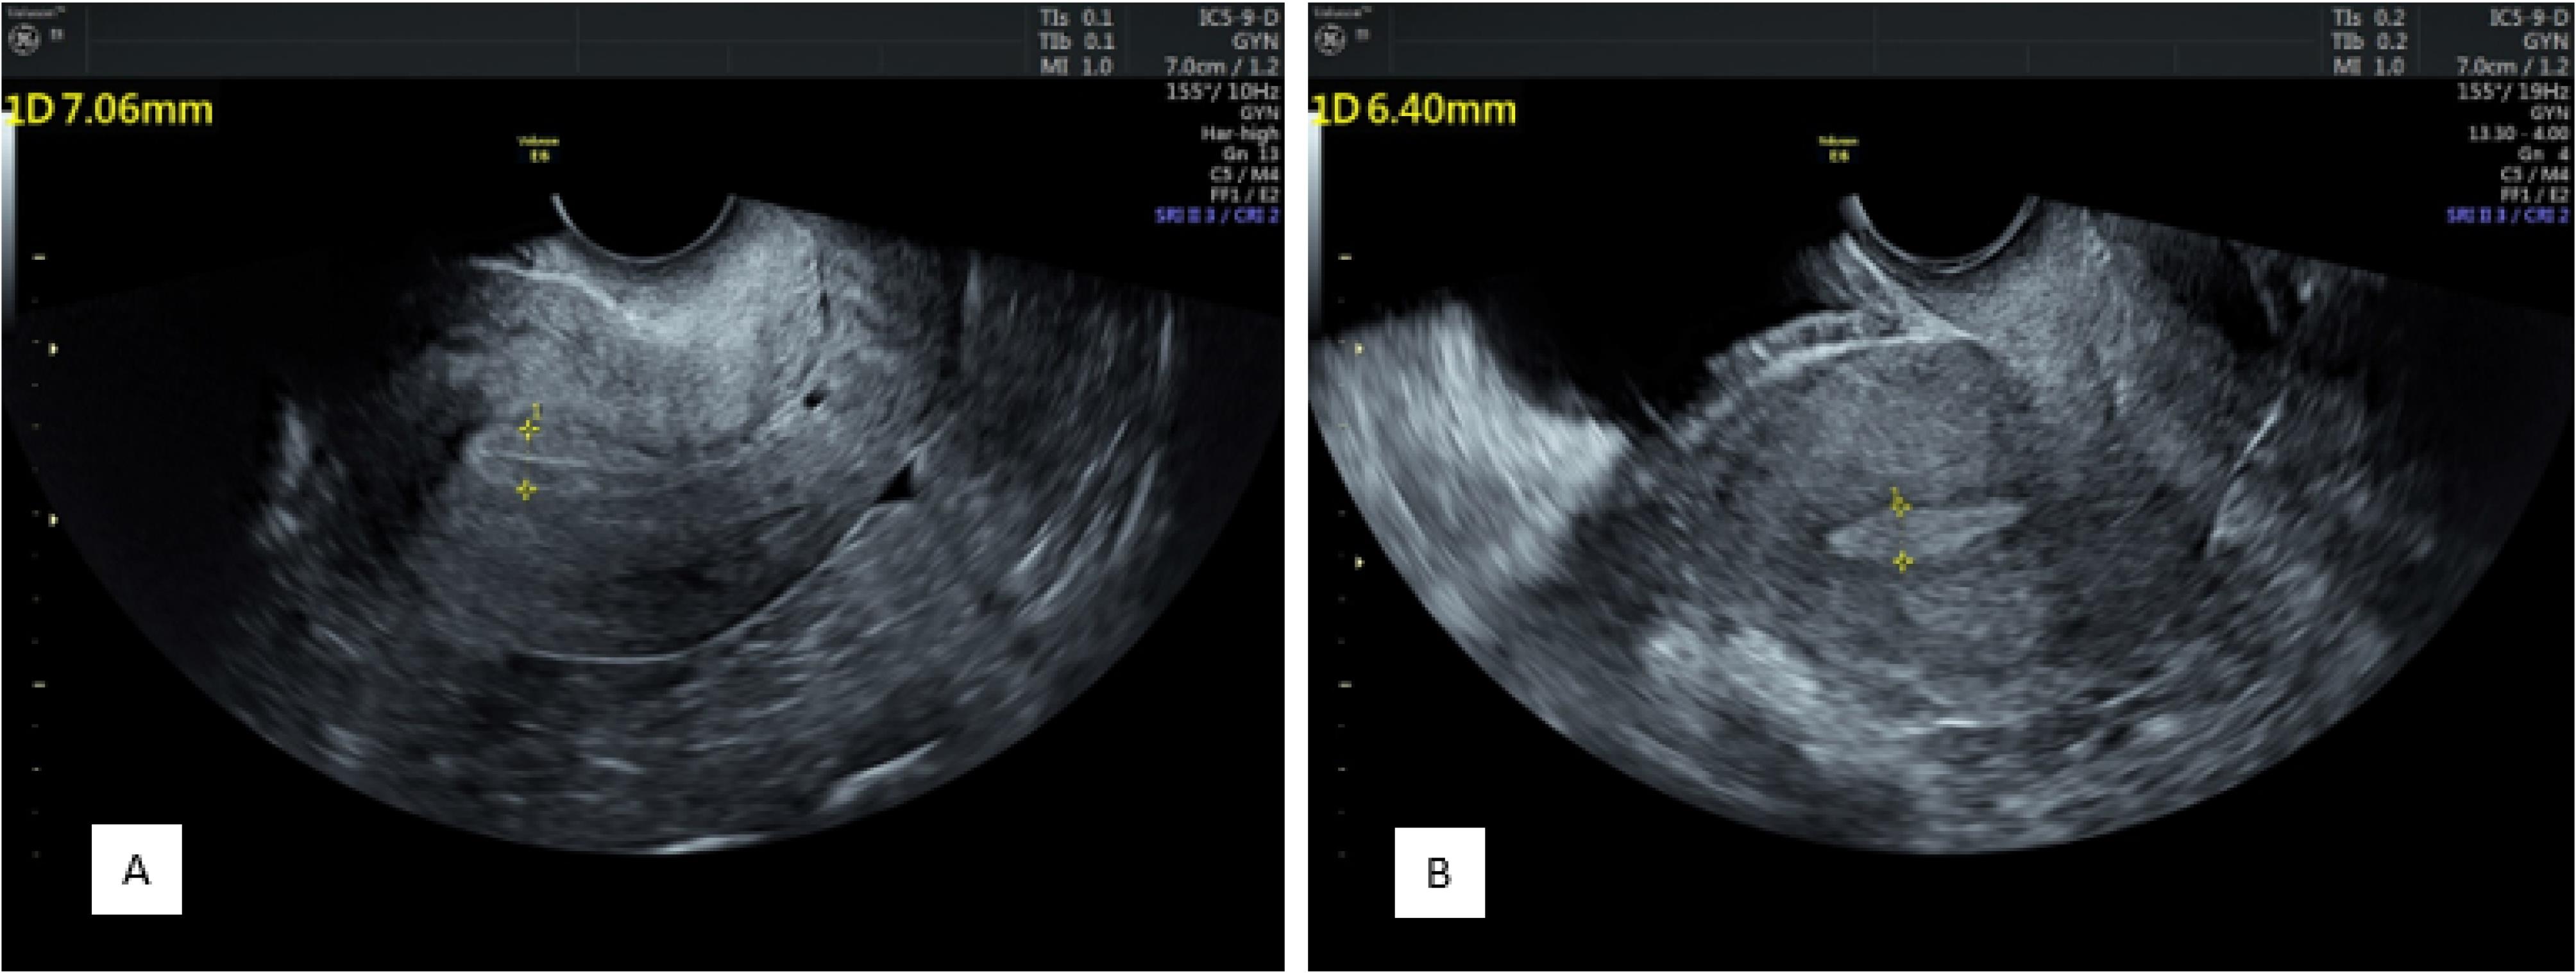

The overall endometrial thickness significantly decreased after progesterone administration (before progesterone administration: 9.66 ± 1.69 mm vs. 8.86 ± 1.76 mm after progesterone administration, P < 0.001). In addition, there were significant changes in endometrial thickness before progesterone administration between the pregnant and nonpregnant groups (10.11 ± 1.97 mm and 9.36 ± 1.39 mm, respectively, P = 0.004). Endometrial thickness was still significantly greater in the pregnant group (9.26 ± 1.94 mm) than in the nonpregnant group (8.59 ± 1.58 mm) after progesterone administration (P = 0.011, Figure 2).

Figure 2.

Endometrial Thickness and View Before (A) and After (B) Progesterone Administration Showing a Decrease in Thickness and Changing From a Clear Three-Layer View Containing a Central Hyperechoic Line Surrounded by Two Hypoechoic Layers to an Endometrium Without Distinguishable Layers

Endometrial Views

Before progesterone administration, 13 patients had an endometrium without layers, 30 had three unclear layers, and 157 had three clear layers. After progesterone administration, the endometrium consisted of 106, 38, and 56 without layers, three unclear layers, and three clear layers, respectively (P < 0.001, Figure 2).

Comparing the appearance of the endometrium before the administration of progesterone in the two groups, in the positive group, 9 were without layers, 14 had three unclear layers, and 58 had three clear layers, and in the negative group, 4 were without layers, 16 had three unclear layers, and 99 had three clear layers (P = 0.056).

Based on the comparison results regarding the appearance of the endometrium after the administration of progesterone in the two groups, in the positive group, 33 were without layers, 9 had three unclear layers, and 39 had three clear layers. In addition, in the negative group, 67 were without layers, 29 had three unclear layers, and 23 had three clear layers (P = 0.002).